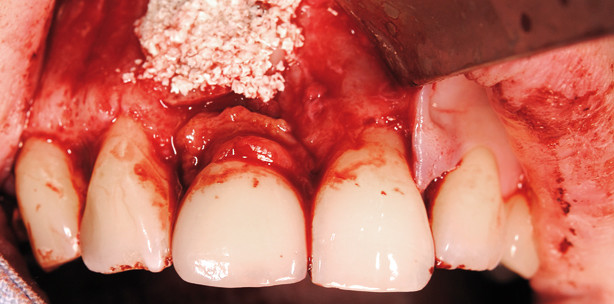

Der Eingriff wurde in Lokalanästhesie unter Sedierung (Dormicum) durchgeführt. Nach marginaler Schnittführung und vertikaler Entlastung in der distalen Prämolarenregion links erfolgten zunächst die Präparation und Mobilisation des vestibulären und teilweise des palatinalen Mukoperiosts. Der intraoperative Befund (Abb. 4 und 5) bestätigte den oben interpretierten Befund des DVT. Nach Darstellung des Situs wurde ein kortikaler Knochenspan vom aufsteigenden Unterkieferast rechts entnommen und mit einer diamantierten Säge entsprechend dem Korrekturbedarf in Regio 11 zurechtgetrimmt und zunächst mit einer 1,0mm starken Osteosyntheseschraube (Stoma-Dentalsysteme GmbH) provisorisch fixiert (Abb. 6). Die gleichfalls vom aufsteigenden Unterkieferast rechts entnommenen spongiösen Knochenspäne wurden anschließend zum Ausgleich des vorhandenen Volumendefizites zwischen den freiliegenden Implantatgewindegängen und dem zu fixierenden Knochenspan eingebracht (Abb. 7). Danach erfolgte die definitive, rotationsstabile Fixation des kortikalen Knochenspanes mit insgesamt drei Osteosyntheseschrauben (Zugschraubentechnik, Abb. 8 und 9). Zur Augmentation und Stabilisierung des marginalen Gingivasaumes wurde ein freies Gingivatransplantat vom rechten Gaumen entnommen und in der angegeben Region fixiert (Abb. 10). Der fixierte Knochenspan wurde zum Resorptionsschutz mit Bio-Oss (Geistlich Biomaterials) gedeckt und abschließend eine Kollagenmembran zum Schutz des gesamten Augmentates eingebracht. Die Abbildung 13 zeigt die Röntgenkontrolle nach Augmentation. Nach komplikationslosem Heilungsverlauf wurden die Wundnähte nach zehn Tagen ­entfernt. Die Dokumentation der Abbildungen 14 und 15 erfolgte 17 Tage postoperativ. Vier Monate nach der durchgeführten Augmentation stellte sich die Patientin zur Recalluntersuchung vor. ­Klinisch zeigten sich vollständig reizlose Wundverhältnisse und ein stabiler marginaler Gingivasaum (Abb. 16 und 17). Zu diesem Zeitpunkt erfolgte in Lokalanästhesie über eine kleine vestibuläre Inzision die Entfernung der primär eingebrachten Osteosyntheseschrauben.